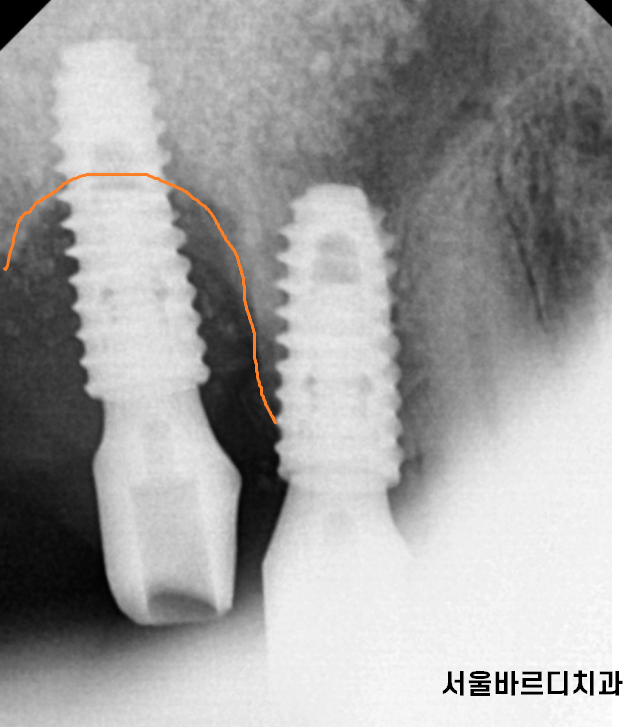

심어둔 임플란트 뼈 높이가

점점 내려가

임플란트가 덜렁덜렁 거리고

임플란트가 이가 빠지듯

쏘옥 빠지게 됩니다.